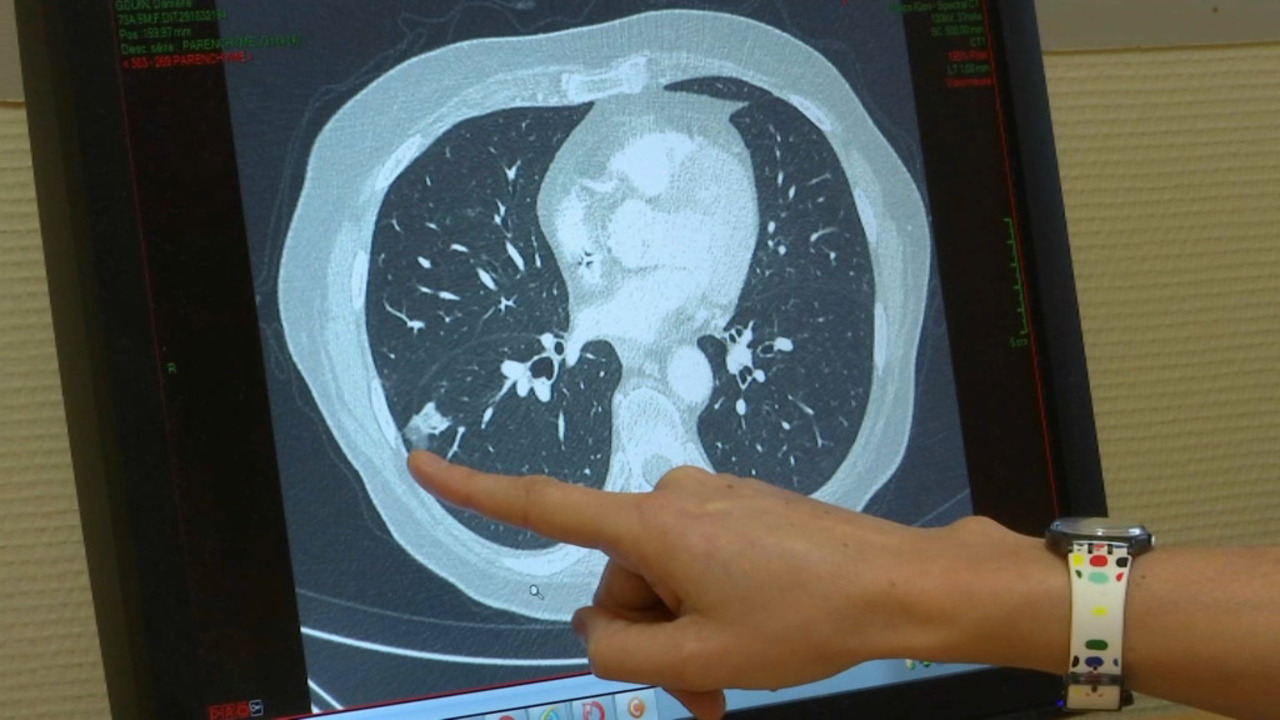

Video Pour Diagnostiquer Le Covid 19 Dans Les Poumons Le Scanner Tourne A Plein Regime

www.ouest-france.fr

Comment Le Scanner Thoracique Permet De Mieux Prendre En Charge Les Malades Atteints Du Coronavirus

www.bfmtv.com

Un Scanner Pour Detecter Le Coronavirus Chez Des Personnes Au Test Negatif Youtube

www.youtube.com